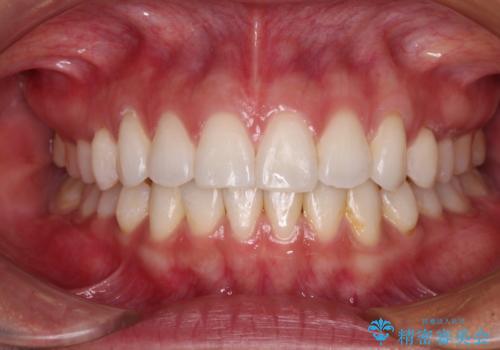

【モニター】インビザラインで口を閉じやすく

- 前に出ている上顎前歯が気になるとのことで来院された患者様です。

インビザラインを用い、IPR(歯と歯の間を削る)と歯列全体を後方に移動させることで、可能な限り前歯の突出感を改善することとしました。

元々の歯列も整っており、横顔の印象の出っ歯ではなかったため、仕上がりに満足できない可能性があると心配しておりましたが、口が閉じやすくなり、患者様には大変満足していただきました。